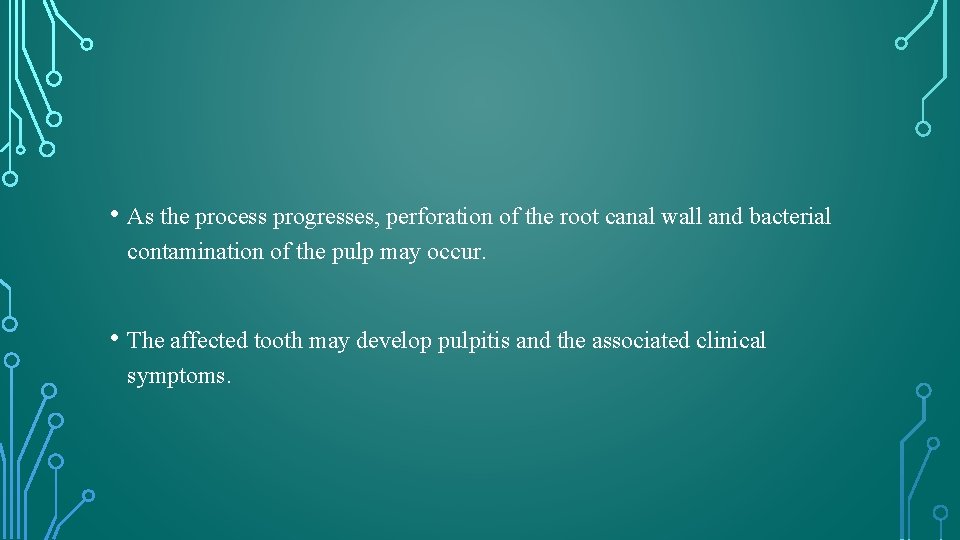

HISTOLOGIC APPEARANCE • Same as that of other forms of resorption , with certain unique feature reflecting the invasive nature of the process. • Narrow “channels” of resorption extend through the dentin and may communicate with the periodontal ligament.

HISTOLOGIC APPEARANCE • Pulpal tissue was populated to varying degrees in all teeth with an inflammatory infiltrate composed predominantly of lymphocytes and macrophages. • The odontoblast layer and predentin were absent from the affected dentinal walls, which were populated by large, multinucleated odontoclasts occupying resorption lacunae. • Islands of mineralized tissue occupying the root canal space are the defining feature of internal replacement resorption.